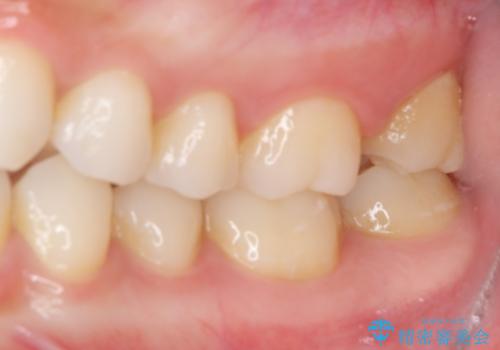

ゴールドインレーは銀歯のインレーやセラミックインレーと比べ、「技工操作の精度が高く、適合が著しく良い」というメリットがあります。特に上の奥歯は歯科医師の操作が行いにくいため、「適合の良さ」は再治療のリスクを防ぐ上でとても重要な要素となります。

上の奥歯は金属色が見えることもないため、審美的な問題は全くありません。

咬み心地はとても良好で、全く違和感がなく、患者様には大変満足していただきました。